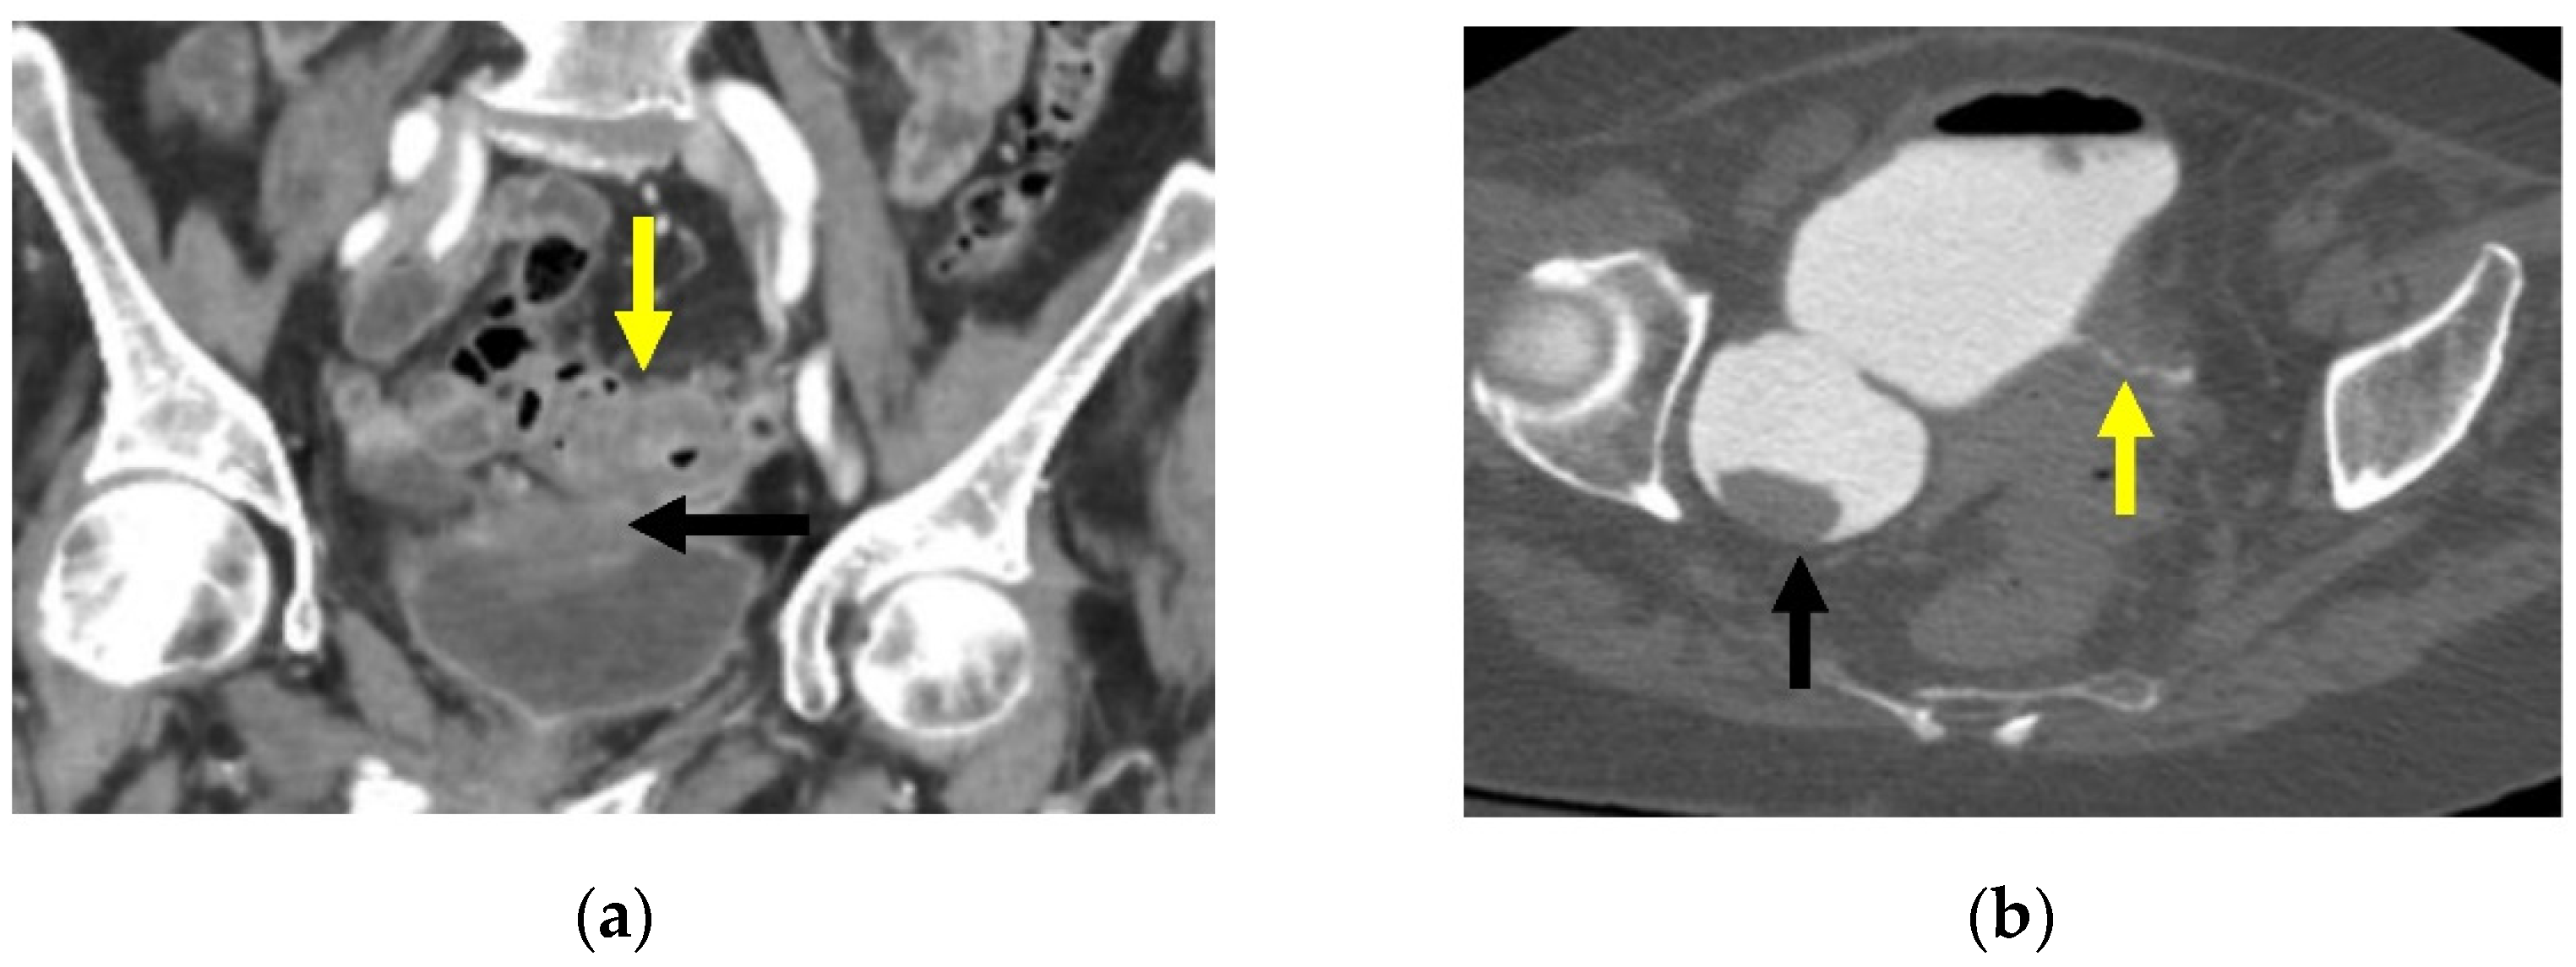

The inflammatory reaction may progress to pericolic and mural phlegmonous infiltration as well as sealed perforation, free perforation, abscess, fistula (Figure 5 and Figure 7a,b), and a stenosing inflammatory sigmoid mass [9]. A fistula develops associated with diverticulitis when a fistulous tract, or connection, forms between the affected colon and another organ, whether that is the bladder, vagina, uterus, skin, or another part of the intestine (see Figure 5 and Figure 7a,b) [8,31]. These patients are often diagnosed clinically, with pneumaturia or a urinalysis growing gut microorganisms (colovesical fistula); foul-smelling vaginal discharge or air and stool from the vagina (colovaginal or colouterine fistula); presence of an enterocutaneous fistula with purulence or stool from the abdominal wall (colocutaneous fistula); or are asymptomatic or with vague abdominal symptoms (coloenteric fistula). On CT, enhancement is also seen along fistulous tracts, making them more conspicuous (Figure 7a). Retrograde opacification of the bladder during a cystogram (Figure 7b) or colon with rectal contrast may also be helpful to define fistulas [27].

Figure 7.

(a). Coronal CT image through the pelvis with IV contrast. There is segmental wall thickening of the sigmoid colon (yellow arrow) with multiple diverticulae. There is contiguous soft tissue density with the superior wall of the bladder (black arrow), suggestive of colovesicular fistula. (b). Axial image from CT cystogram. The bladder has been filled with contrast via Foley catheter. Tract is confirmed between the bladder and sigmoid colon (yellow arrow). There is also a large bladder diverticulum (black arrow).